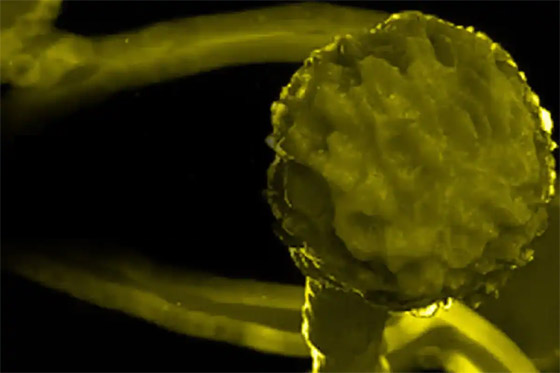

في حين لا يزال الأطباء يكافحون حالات انتشار الفطر الأسود والأبيض لدى مرضى كورونا، بدأ نوع ثالث من العدوى الفطرية بالانتشار في أوساط المرضى في الهند على وجه التحديد. نتحدث هنا عن مرض الفطر الأصفر، فما هي أعراضه وأسبابه؟ وما هو وجه الاختلاف بينه وبين الفطر الأبيض والأسود؟

الفطر الأصفر.. هل هو عدوى جديدة؟

ما هو الفطر الأصفر؟

يغزو الفطر الأصفر الأعضاء الداخلية للجسم ويؤثر على أدائها الوظيفي بالكامل، ولا ينطلق الفطر الأصفر من الرئتين بالضرورة، ويتشكل بسبب وجود نوع من الفطريات التي تتكاثر لتهاجم الجسم بأكمله. قد تترافق الإصابة بالفطر الأصفر بالطفح الجلدي وحرقة الجلد والإرهاق، ومن الممكن أن يصبح شديداً وخطيراً للغاية إذا لم تتم معالجته بسرعة. ويعتمد مدى انتشار الفطر الأصفر في جسد المريض على حالة المريض الصحية وقوة مناعته، ولكيلا يصبح الأمر خطيراً ينبغي التركيز دائماً على الوقاية من هذا المرض.